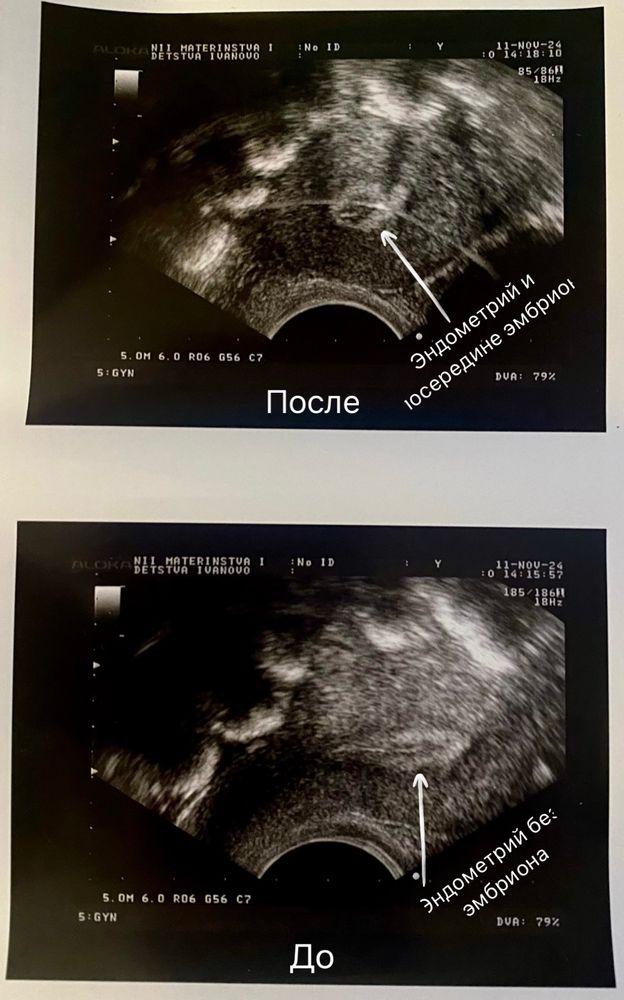

Подсадили эмбриончика, во время процедуры сделали снимки УЗИ до (снизу) и после (сверху).

Сказали очень хороший получился эмбрион, даже сияет на снимке✨ (это светлая полоса посередине кружочка эндометрия + сверху видна от эмбриона хорошая тень). Мой врач-репродуктолог говорит впервые такое видит, это нормально)). Теперь главное чтобы эмбрион подружился с эндометрием и прижился)🙏